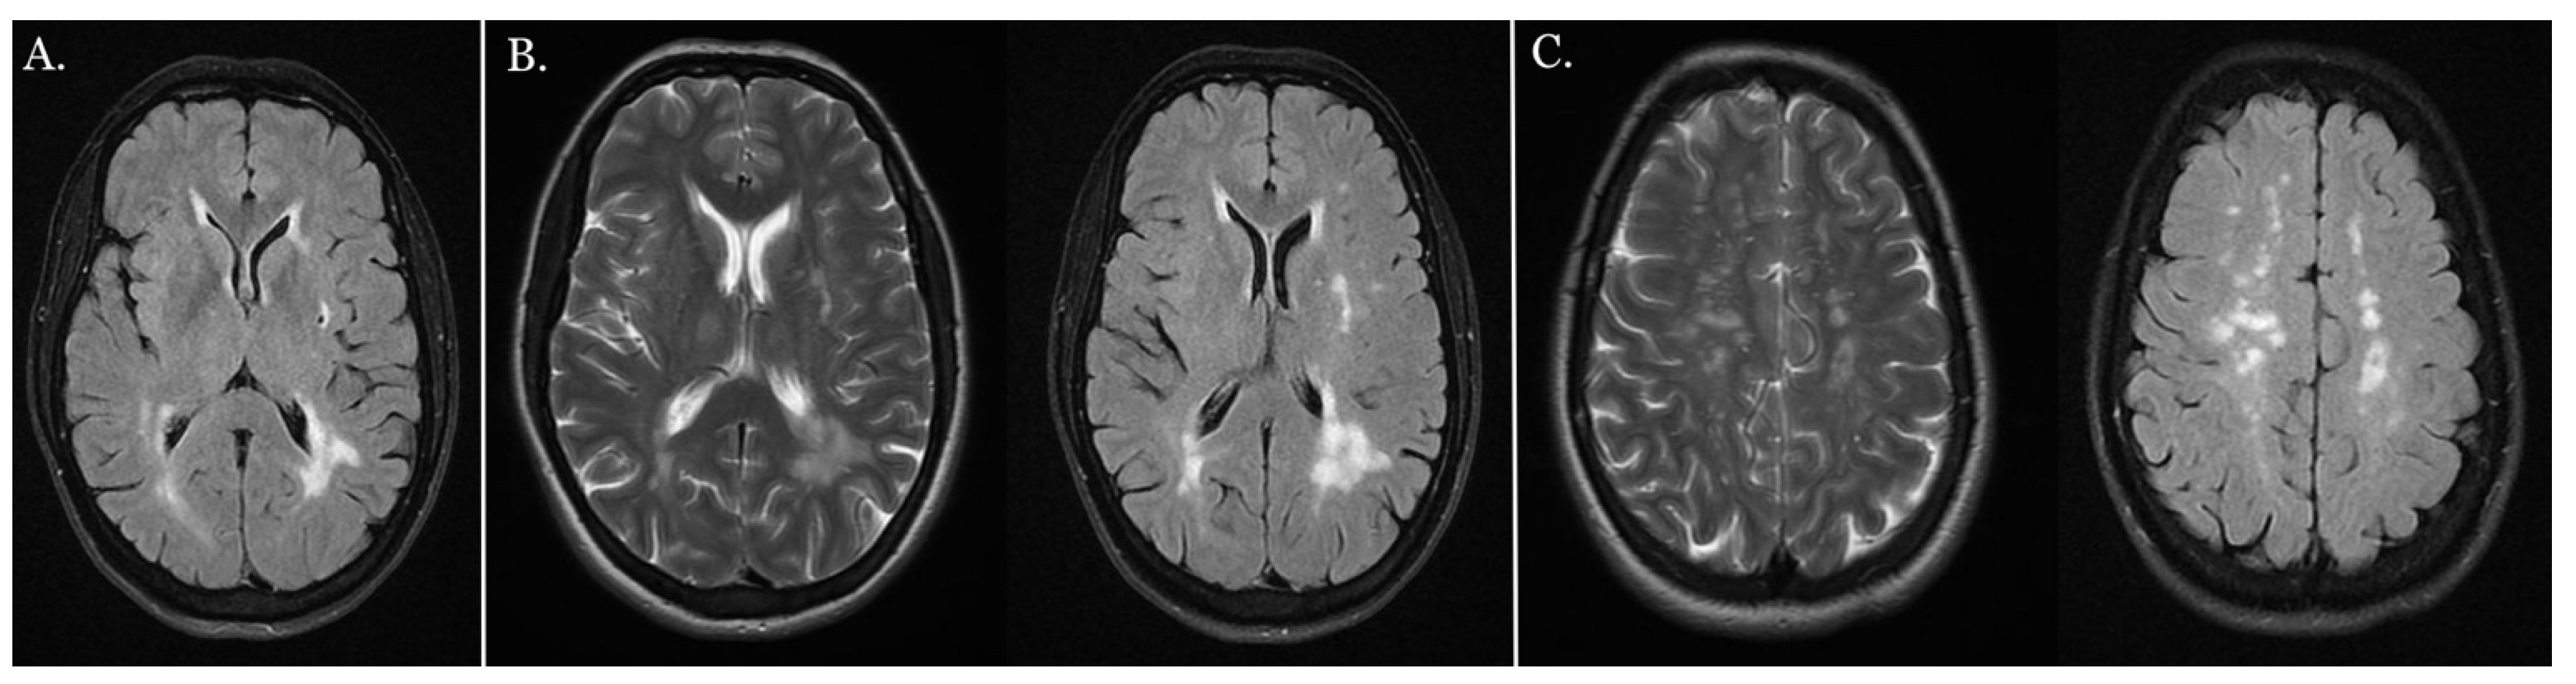

An MRI of the central nervous system showed multiple focal vasogenic lesions in the white matter of both hemispheres, which were partly merged in the occipital horn region (Figure 7B). A single microinfarct lesion was found in the left external capsule (Figure 7A).

Figure 7.

MRI of the central nervous system. (A) Single focal subcortical microinfarct in the left external capsule shown in MRI-FLAIR image. (B) Subcortical and periventricular areas of the white matter of the brain shown using MRI, along with multiple focal vasogenic lesions in the white matter of both hemispheres, partly merged in the occipital horn region (LS: MRI-T2 image, RS: MRI-FLAIR image). (C) The formation of pathological changes mainly in the white matter of the brain shown in MRI (left side (LS): MRI-T2 image, right side (RS) MRI-FLAIR image).